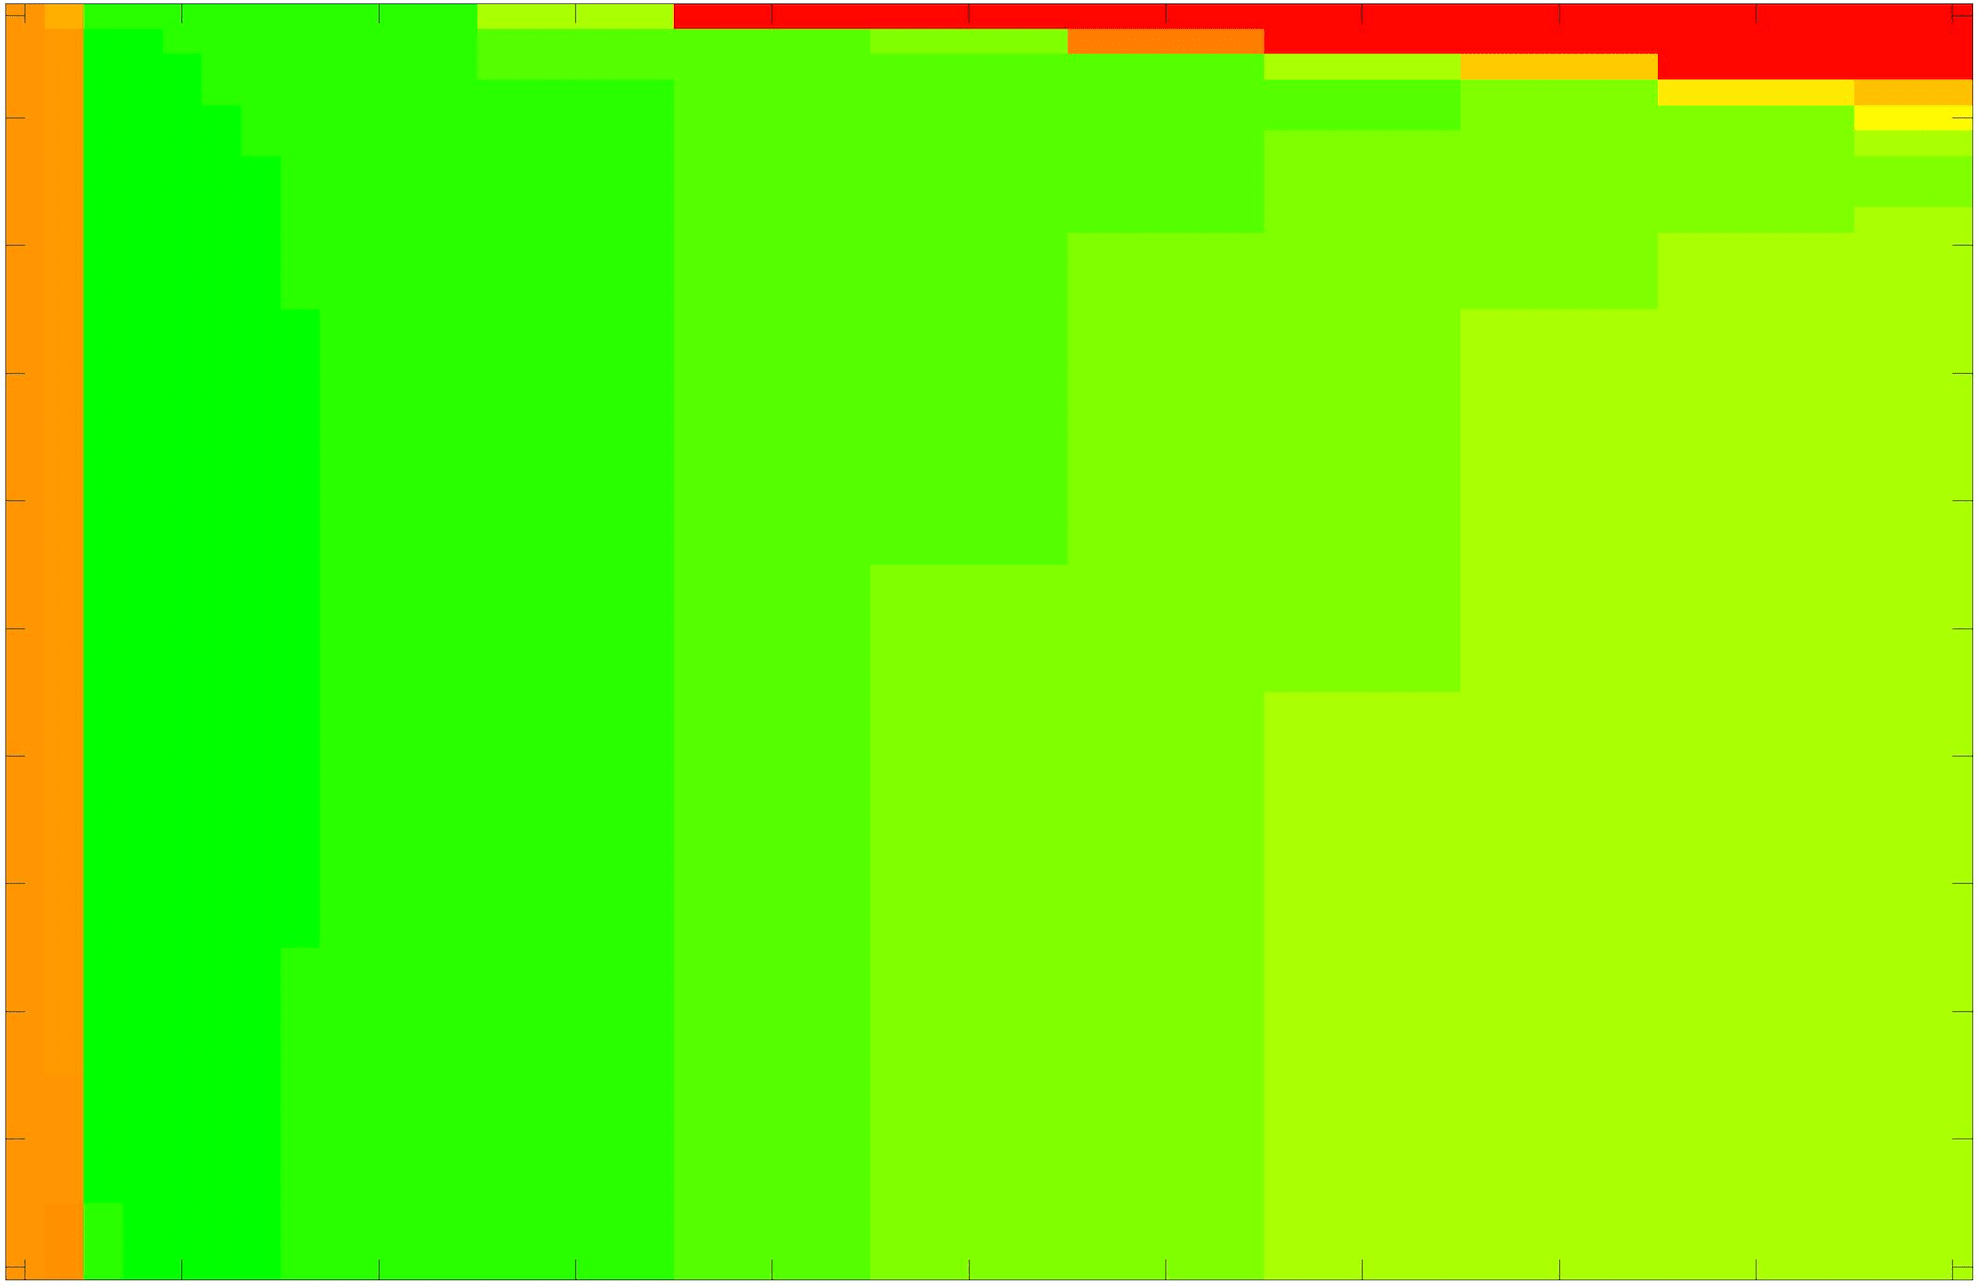

where refers to the number of points in the enclosed region. This takes values in the range , with higher TC values indicating a more accurate segmentation. In the following we will represent accuracy visually from red () to green (), with the intermediate scaling of colours used shown in Fig. 8. This will be particularly relevant in §7.2.

The TC values for the parameter sets are presented as heatmaps in Figs. 11–13. A heatmap is a convenient way to display accuracy results for hundreds of tests concisely. In Fig. 9 we give an example heatmap with the same axes used for those in Figs. 11–13. For each of the combinations of parameter values we give the TC value of the segmentation result and represent it by the appropriate colour. The corresponding colour scale is shown in Fig. 8. Qualitatively, the more green areas of the heatmap the more accurate the model is for a wider set of parameters. Example results for Test Image 5 when varying (with ) for the proposed model are given in Fig. 10. Here it can be seen what each accuracy result corresponds to visually.

Note. The axes have been removed from the heatmaps in Figs. 11–13 for presentational clarity. However, to be explicit, the axes used in all heatmaps are the same as those in Fig. 9.

Synthetic Images. These results are presented in Fig. 11. For Test Images 1–2 we see poor parameter robustness from all competing models, except for GAV which performs reasonably well. However, the proposed model has minimal parameter sensitivity for these images, with good results achieved for almost every combination of values tested. For Test Image 3 all models have a reasonable parameter range (except for RSF), however the proposed model gives better quality results for a wider parameter range. The other models achieve reasonable results here as the foreground intensity of the ground truth is greater than the background , whereas for Test Images 1–2 they are equal . These results highlight the key advantage of the proposed model.

Real Images. In Fig 12 we present results for Test Images 4–6. Here, the proposed model performs in a similar way to its competitors because these images are more typical selective segmentation problems in the sense that there is a clear distinction between the foreground and background intensities. In particular, the values in each case are: Test Image 4 , Test Image 5 , and Test Image 6 . It can be seen that the proposed model is competitive compared to previous approaches. The performance is quite poor for Test Image 5, but is arguably still the best for this challenging case. In Fig. 13 we present results for Test Images 7–9. Here the proposed model outperforms previous approaches significantly for each image. This is mainly due to the type of image considered. Specifically, the true intensities are: Test Image 7 , Test Image 8 , and Test Image 9 . The proposed model is capable of achieving results where , with other models failing completely in these cases.